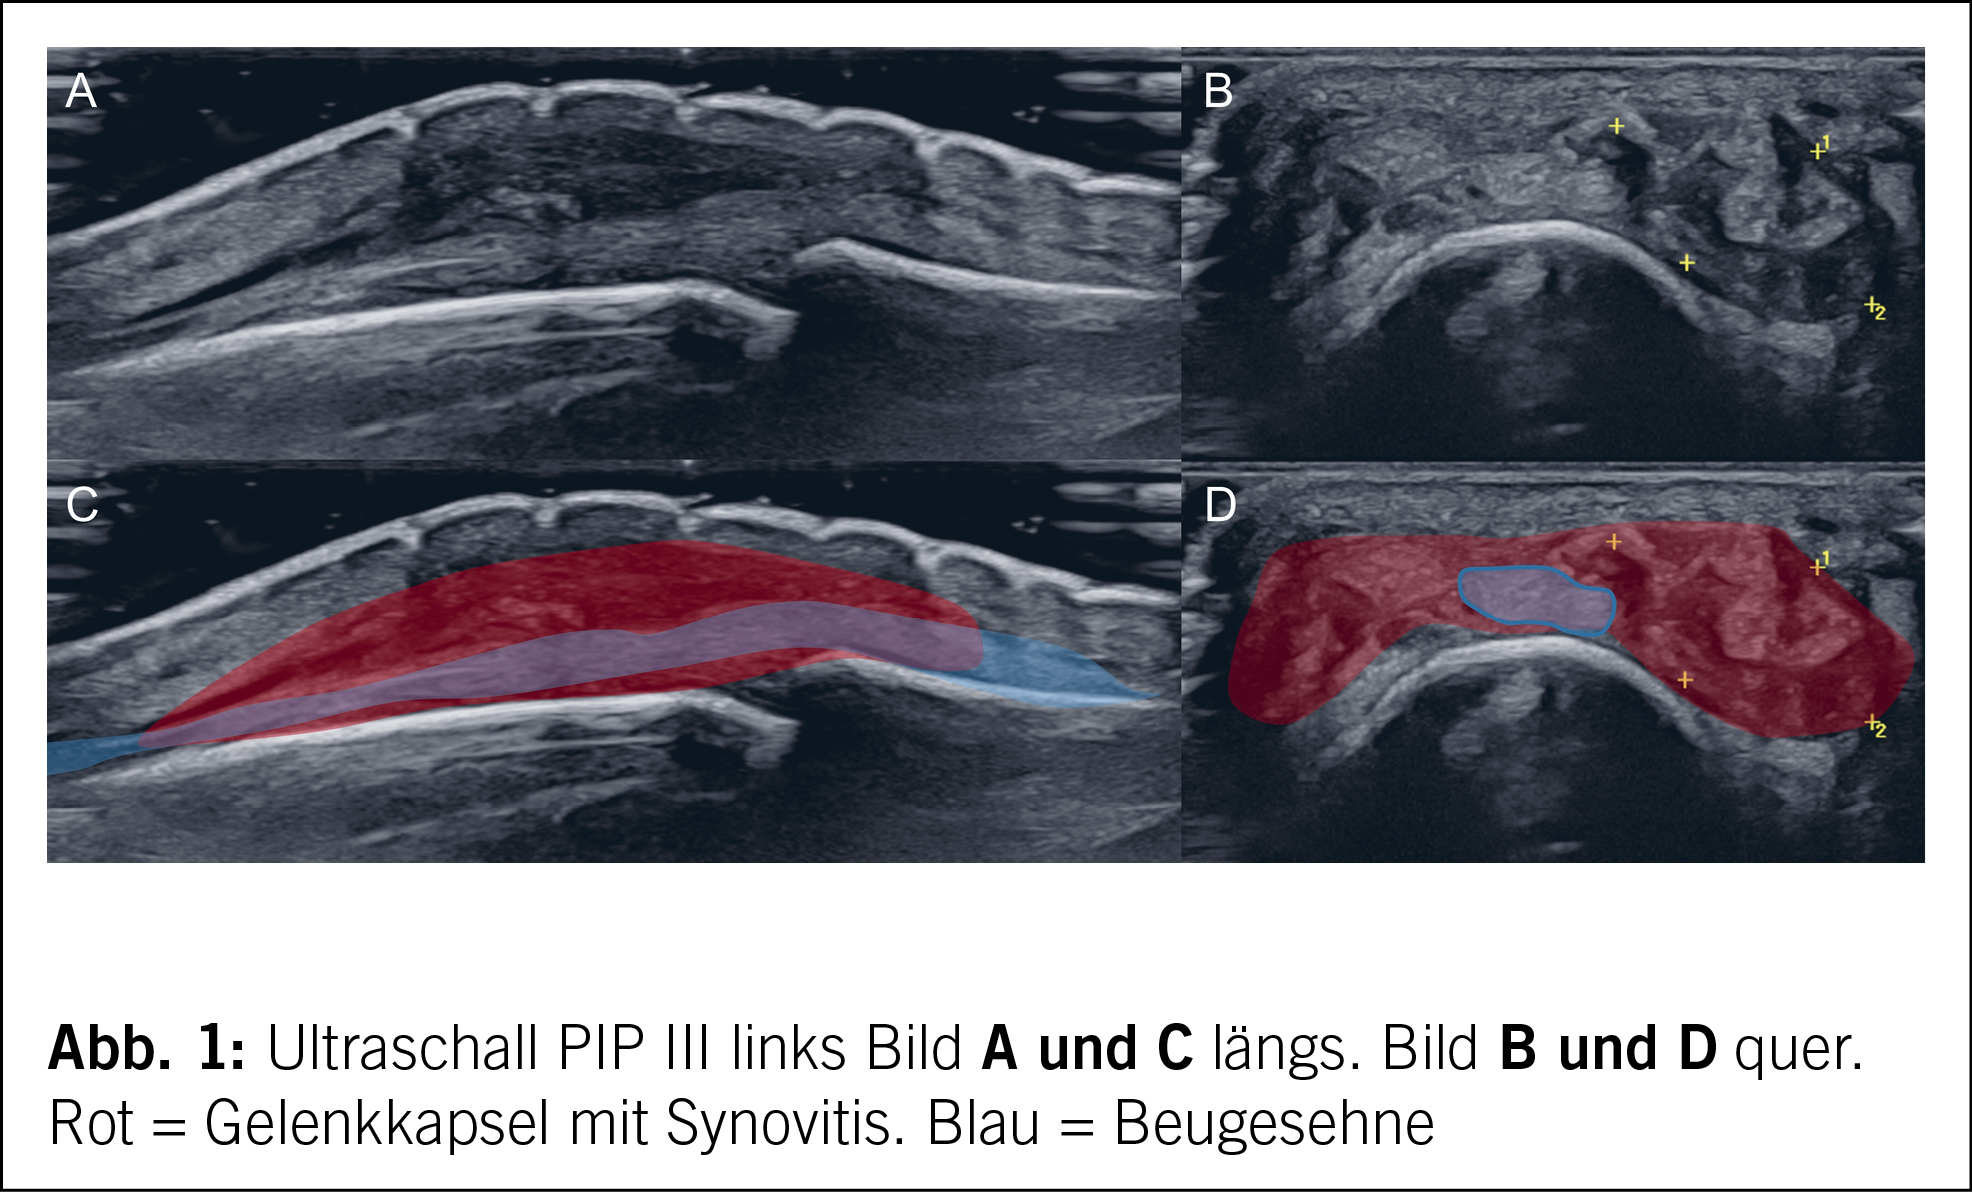

Bei akuter Monoarthritis entschieden wir uns bei fehlender Punktionsmöglichkeit pragmatisch bei bekannter undifferenzierter Polyarthritis für eine Infiltration mit 10 mg Triamcinolon acetonid (Kenacort). Nach initialer Besserung manifestierte sich nach einigen Monaten eine erneute Arthritis im gleichen Gelenk sowie zusätzlich eine Arthritis im PIP III der rechten Hand (Abb. 1).

Bei fehlender Krankheitskontrolle unter der Therapie mit Methotrexat (> 6 Monate) und Glukokortikoiden entschieden wir uns bei Zweifel an der Diagnose einer rheumatoiden Arthritis für eine weiterführende Diagnostik mittels ultraschallgesteuerter Synovialbiopsie des PIP III links. Differenzialdiagnostisch kamen bei der Patientin mit zwei vorbestehenden Geschlechtskrankheiten eine reaktive Arthritis im Rahmen der bestehenden HIV-Infektion, eine neu aufgetretene Infektion mit Chlamydia tracheomatis oder Neisseria gonorrhoea, eine Arthritis im Rahmen der Hepatitis B und eine Kristallarthropathie in Betracht. Wobei in den Blutkontrollen der letzten Jahre keine HBV-DNA nachweisbar war und die HIV-Viruslast unter antiretroviraler Therapie konstant unter 50 Kopien HIV-RNA/ml lag und diese somit unwahrscheinlich waren.